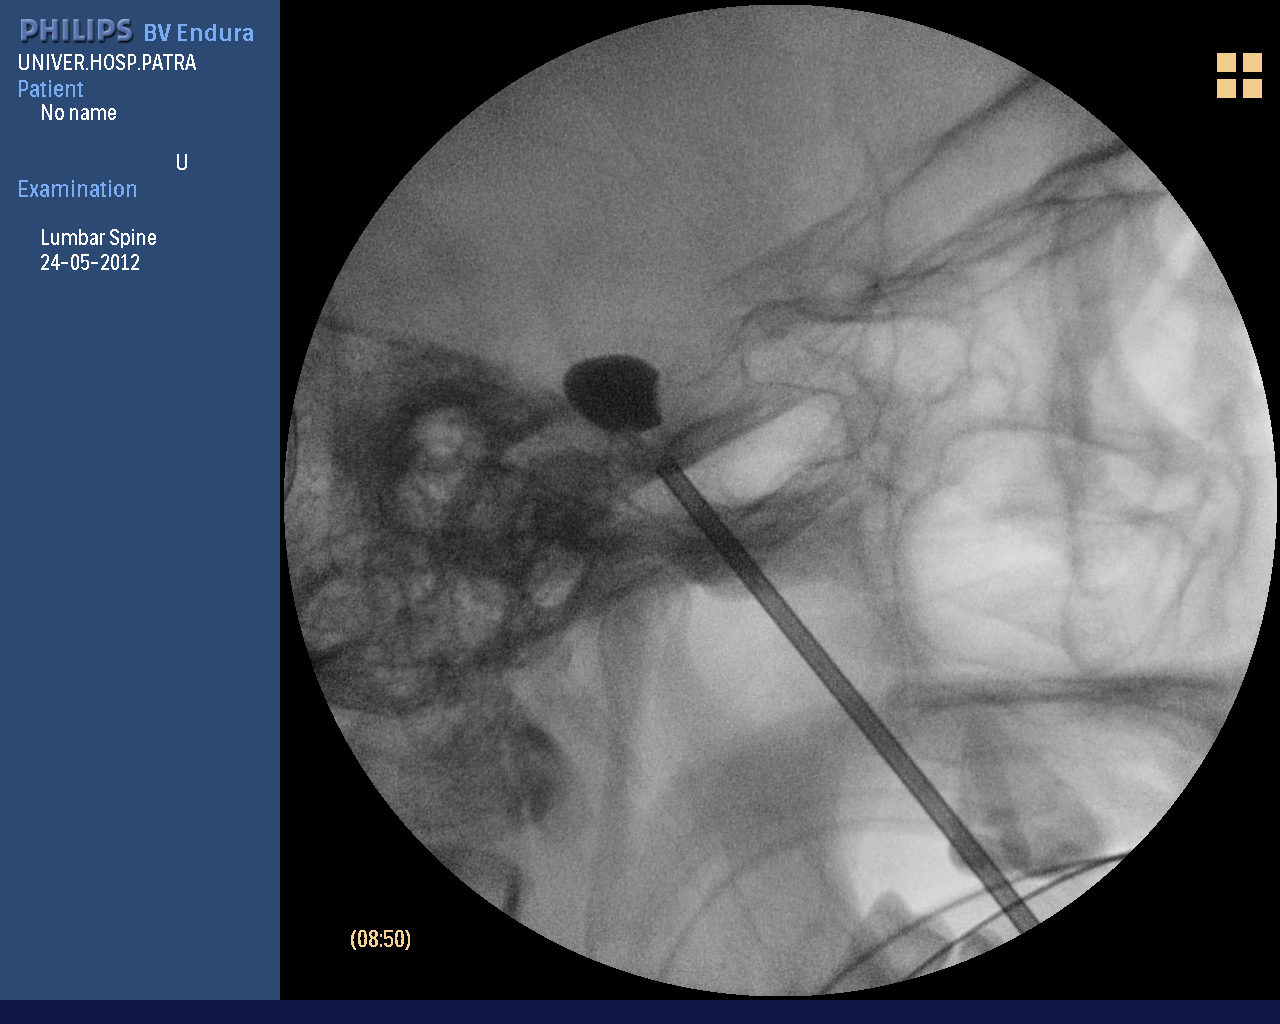

Percutaneous balloon compression (BC balloon compression)

Balloon compression is a percutaneous method in which a microcatheter is inserted into the trigeminal ganglion and a balloon is inserted and a balloon is used to stretch and destroy the nerve fibres. It is the method of choice in older people, has minimal side effects and provides immediate pain relief. Pain remission usually lasts for 5 years. It is performed under general anaesthesia for 30 minutes.

View of the operating room during percutaneous balloon compression.

Percutaneous balloon compression for trigeminal neuralgia

Percutaneous technique for trigeminal neuralgia.